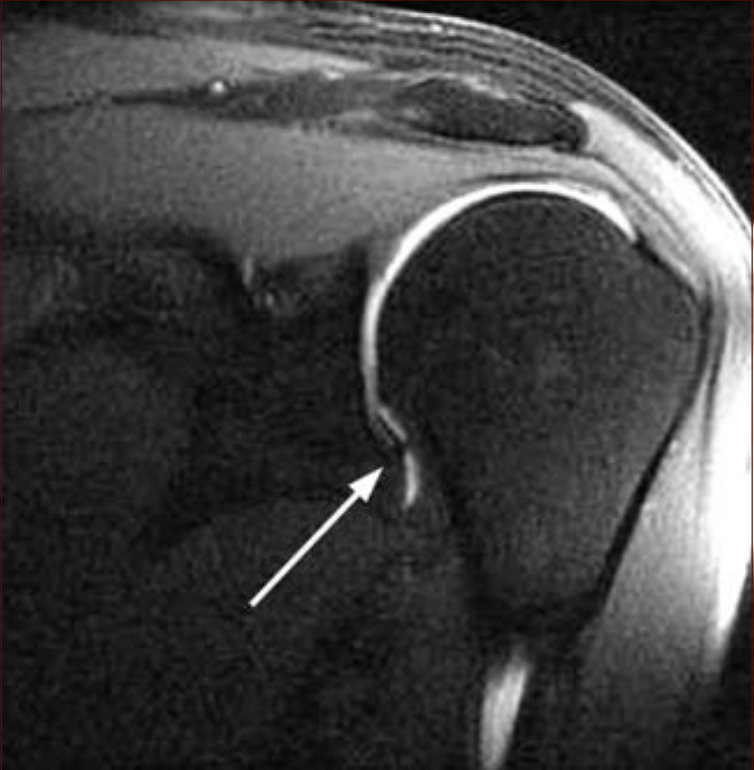

50견 환자의 수축캡슐과 하부소실을 보인 MRI

관절낭의 유착을 보이다